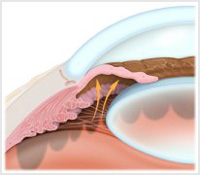

پژوهشگران کشف کرده اند که گرفتن سرخک حتی خطرناکتر از آن چیزی است که دکترها متوجه شدهاند، زیرا باعث میشود که قربانی به بیماریها ...